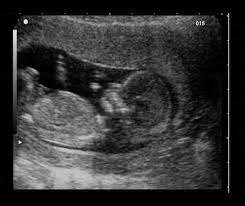

• Period: to

Weeks 7/8

The brain and face begin to grow. The 4 chamber heart- lungs begin to form. Fingers and toes being to form.